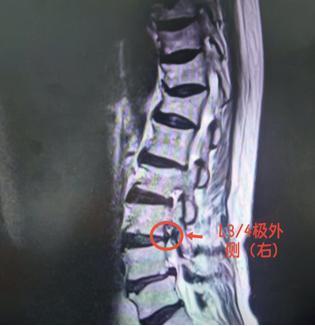

看着父亲日渐消瘦,儿子经人推荐,带他来到石门县人民医院脊柱外科求治。副主任医师王强仔细检查后,盯着 CT 片子皱起眉头:“您的突出物‘跑偏’了,躲进了神经根出门的‘门缝’里!”

原来,陈大爷得的是 “极外侧型腰椎间盘突出”—— 这是一种仅占腰椎间盘突出症 4.1%~11%、却极易被漏诊的特殊类型。

检查易 “漏网”:常规 CT 平扫横断面上,椎管内无明显异常,需通过薄层 CT 精确扫描椎间孔内及外侧区,才能发现低密度软组织团块;MRI (核磁共振)上则可见椎间孔内神经根显影不清、受压迫。